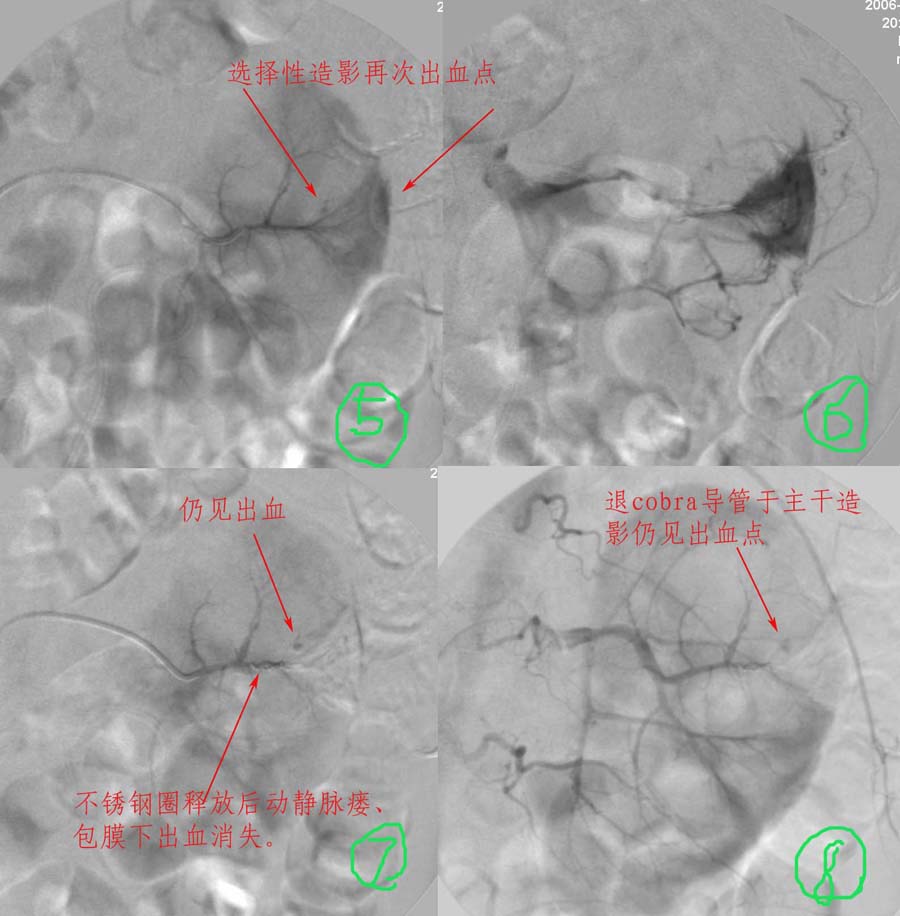

介入治疗过程:

注:图5\6文字标示应为".....再次证实出血部位"

准确的出血部位请参考\"介入治疗过程\"图片标示!